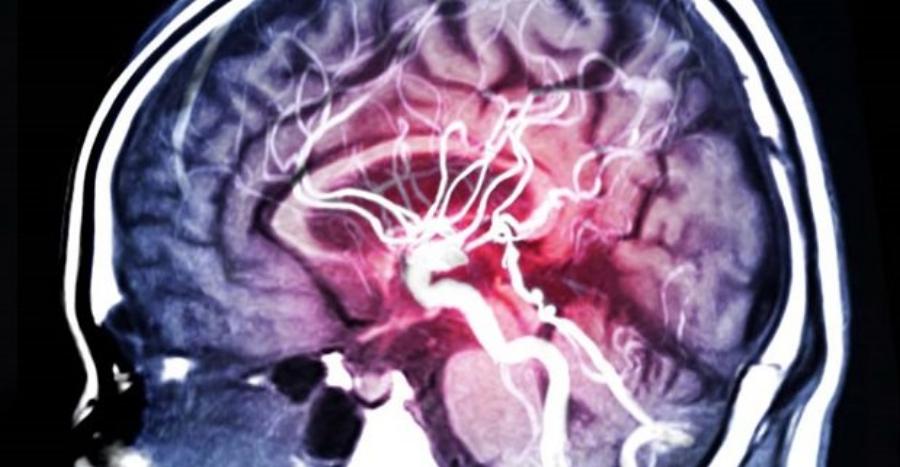

Το ανεύρυσμα εγκεφάλου μοιάζει με ένα μικρό μπαλόνι που μπορεί να «σκάσει» οποιαδήποτε στιγμή και η ρήξη του ανευρύσματος αποτελεί επείγουσα κατάσταση. Εάν το ανεύρυσμα έχει σχηματιστεί σε αιμοφόρο αγγείο του εγκεφάλου, η ρήξη συνεπάγεται ότι διαρρέει αίμα στους γύρω ιστούς.

Το ανεύρυσμα είναι ένα παθολογικό «φούσκωμα» σε μία από τις μεγάλες αρτηρίες του εγκεφάλου. Το «φούσκωμα» αυτό έχει σαθρά τοιχώματα, και κάποια στιγμή μπορεί να σπάσει. Λίγες φορές τα ανευρύσματα του εγκεφάλου οφείλονται σε λοιμώξεις, σύνδρομα ή άλλα αίτια.

– Η διάγνωση της κατάστασης μπορεί να γίνει άμεσα με επείγουσα αξονική τομογραφία (CT) εγκεφάλου που δείχνει την αιμορραγία, και μπορεί επί τόπου να συμπληρώνεται με αξονική αγγειογραφία που θα δείξει και το ανεύρυσμα εγκεφάλου. Συνήθως ακολουθεί και ψηφιακή αγγειογραφία εγκεφάλου (DSA).

Έτσι μπορεί να θεραπευτεί πριν σπάσει. Γι’ αυτό οι νευροχειρουργοί εδώ και χρόνια προτείνουν να γίνεται προληπτικός έλεγχος με μαγνητική αγγειογραφία (ΜRA) εγκεφάλου σε όλον τον πληθυσμό.